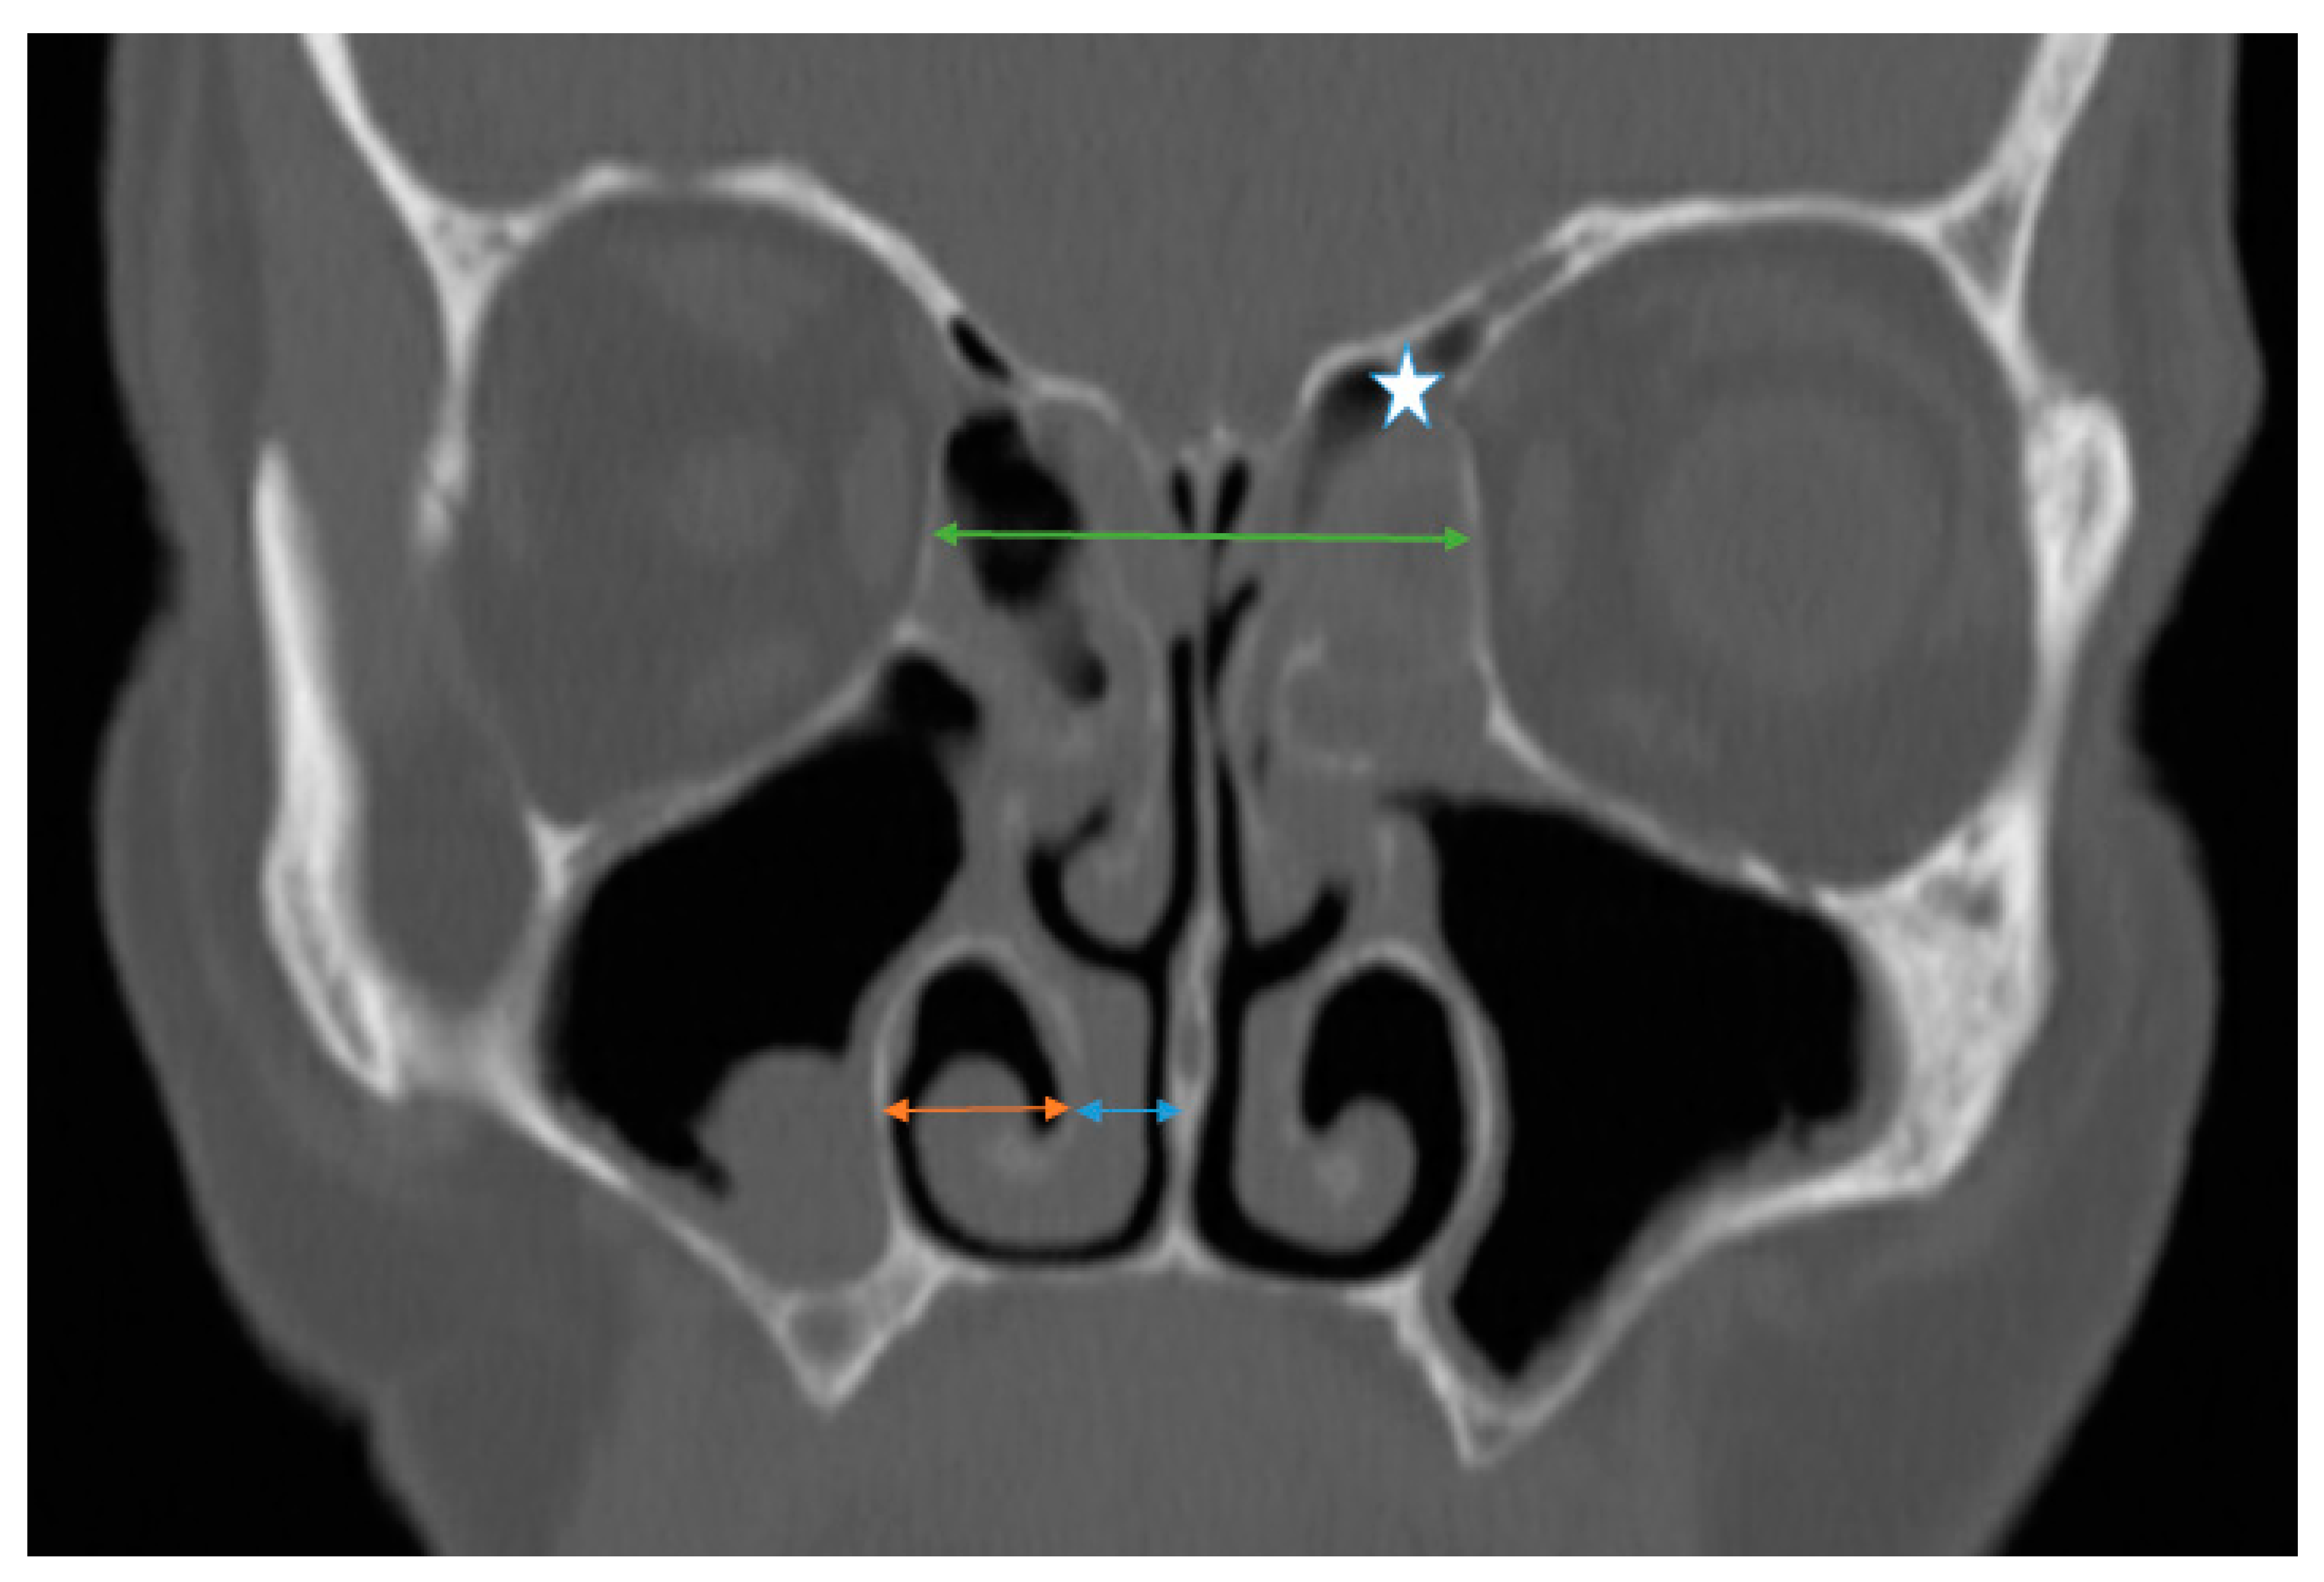

2.1.1. Inferior Turbinate Position

To assess the radiological position of the inferior turbinate, several measurements were performed bilaterally using the CT scan (coronal plane). These measurements comprised the following: 1. The horizontal distance between the lateral border of the IT bone and the lateral nasal wall (ITL). 2. The distance between the medial border of the IT bone to the median nasal line (vertical line from the crista galli to the nasal spine) (ITM) (Figure 1). The point of entry of the anterior ethmoidal artery into the nasal cavity (nipple sign) served as an anchoring point to produce reproducible and accurate measurements in both the baseline and post-ESS CT images.

2.1.3. Lamina Papyracea (LP) Position

To investigate the effect of ethmoidectomy on the LP position we performed several measurements: in the coronal plane, a vertical line was drawn from the crista galli to the nasal floor, then a perpendicular line was drawn from one lamina papyracea reaching the contralateral lamina passing through the nasal septum at the level of the cribriform plate. The distance between the two laminae on the coronal CT scan was defined as the interorbital distance (IODcoronal). The point of entry of the anterior ethmoidal artery into the nasal cavity (nipple sign) served as an anchoring point to produce reproducible and accurate measurements in both the baseline and post-ESS CT images (Figure 1).

Figure 1. Sinus computed tomography scan, coronal plane. Star: the left anterior ethmoid artery. Green line: IOD in the coronal plane (IODCoronal). Orange line: distance between the lateral border of the inferior turbinate to the lateral nasal wall (ITL). Blue line: distance between the medial border of the inferior turbinate and the septum.